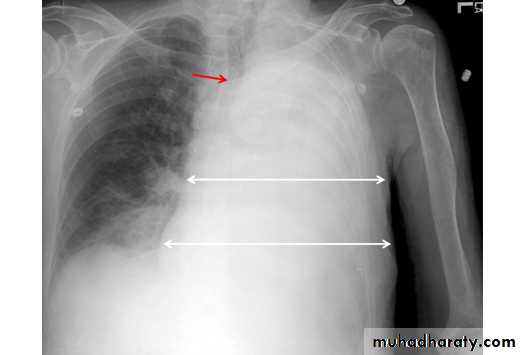

Pleural effusion

50.pleural effusion

51.pleural effusion .